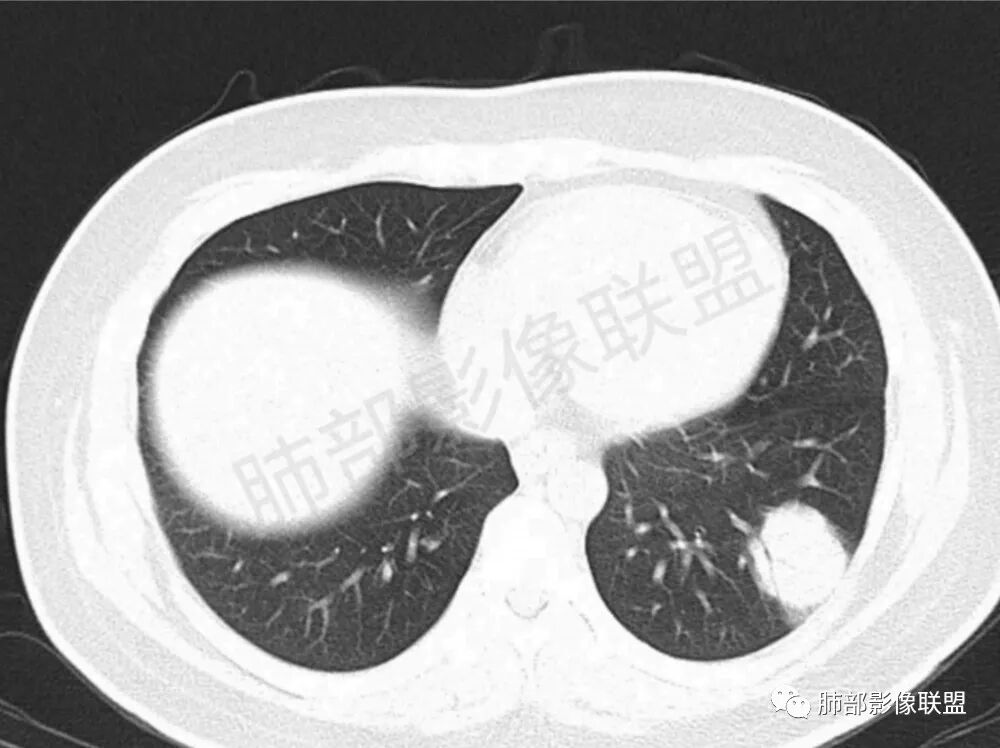

男性,22岁,HIV病史,症状半年,双肺多发大小不等结节影,边缘光滑,密度均匀,以胸膜下分布为主,部分与胸膜相连,胸膜下脂肪间隙可见,病灶近段支气管走行病灶内,远端似有堵塞,无增强图像,考虑隐球菌,鉴别:淋巴瘤,GPA

双肺多发结节影,膨隆,边缘光滑,圆顿,沿支气管血管束分布为主,部分贴胸膜,部分见空洞,空气支气管征

两肺多发结节性,大部分位于胸膜下,部分结节周围可见晕征。局部结节内可见扩张的支气管,纵隔淋巴结大,脾大,22岁男,HIV阳性,常规先考虑隐球菌。鉴别淋巴瘤,结核,马儿。

男,22,半年前咳嗽伴少痰,查HIV阳性,痰查TB阳性,既往有肺部斑片影伴空洞、纵隔淋巴结肿大、脾大。SCC、CA50、CA199、FER增高,此次胸部CT:两肺多发结节影,部分沿血管束分布,部分贴胸膜下,大小不一,密度不一,部分较散、边缘模糊,部分较实、圆钝、周围模糊晕,部分结节有支气管进入穿行自然,部分结节有血管分支自如通过。考虑HI∨相关淋巴增殖类病变,淋巴瘤?LYG?鉴别PC、TB。

1.双肺多发大小不一结节,外围为主,边界尚清,部分周围似有GGO

2.类圆形,部分与胸膜相连,糊墙

3.支气管通畅或近端堵塞

影像学缺乏特征性,以支气管血管周围、胸膜下及双肺下叶周边多发结节影最多见,结节易坏死形成空洞,伴有游走性和多变性的特征,结节周围可有磨玻璃样晕征,有时也可见单发结节影、薄壁的囊状阴影或弥漫性浸润影。肺门、纵隔淋巴结肿大少见, 可见胸腔积液和气胸。

肿块型∶表现为两肺多发大小不等的不规则肿块,肿块边缘不光整、欠锐利,有大的分叶,毛刺少见,增强扫描呈明显强化,可合并坏死、空洞;

结节型∶表现为两肺多发大小不等的结节,以两肺中下野多见,结节边缘欠锐利;